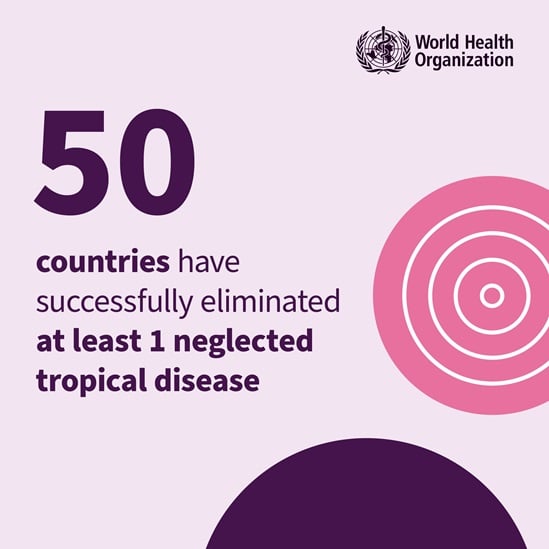

On World Neglected Tropical Disease Day 2024, WHO is calling on everybody, including leaders and communities, to unite and act to address the inequalities that drive neglected tropical diseases (NTDs) and to make bold, sustainable investments to free the estimated 1.62 billion people, in the world’s most vulnerable communities, from a vicious cycle of disease and poverty.